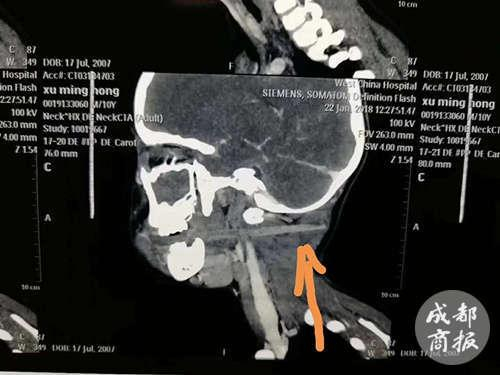

“当时是送到我们的急诊科。”四川大学华西医院耳鼻咽喉头颈外科住院总医师王海洋介绍说,插入宏宏喉咙的异物,是从口腔进入,到口咽部,斜向后上方,从右侧的颈椎旁穿过,在两根重要的动脉之间,“从脖子后面,可以摸得到突起。”万幸的是,因为筷子是圆钝物体,并不尖锐,避开了大的血管,没有造成大出血的情况,这为宏宏能坚持到医院赢得了时间。

幸运的是,手术比较顺利,医生先将露出口腔的筷子部分夹断,再将其余部分,从创伤腔口处慢慢退回,没有伤到大的血管和神经。经过约2个小时的手术,筷子被顺利取出,“我们量了一下,进入身体的筷子长度是10.5厘米,差不多是整个颈部的厚度。”王海洋说。